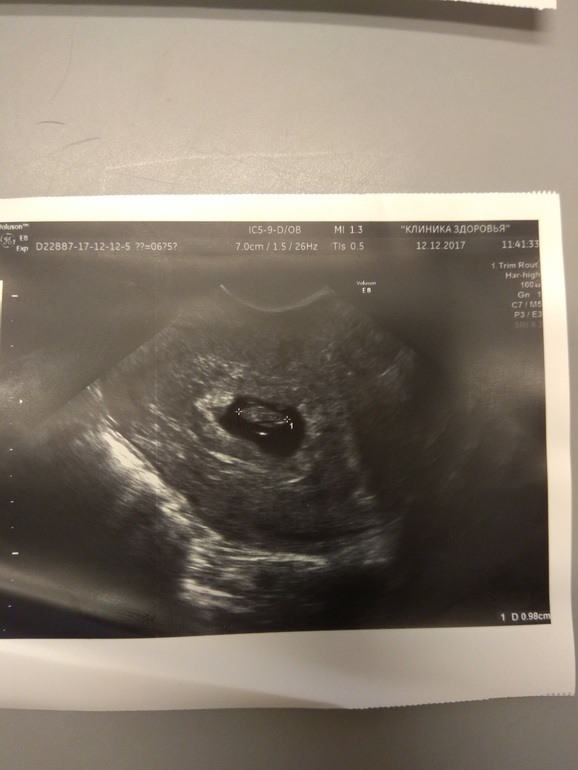

первая картинка-последнее узи последняя картинка-первое узи средняя картинка-оба УЗИ: первое УЗИ (вверху) и второе УЗИ (внизу)

Поняла) Лен,у тебя ПЯ на узи от 12.12 прям хорошее, ттт. И эмбриончику там прям свободно. Замер яйца не совсем мне кажется корректный был. Или действительно, свд замерили - средний внутренний диаметр. А если отрезком мерять - то по длине ПЯ точно мм 20, а то и более даже. Я боялась, вдруг эмбрион быстрее яйца растет и как бы тесно там, но даже по фото этого нет. Расслабляйся и выдыхай давай! По узи хорошо у тебя, и по размерам догоните!